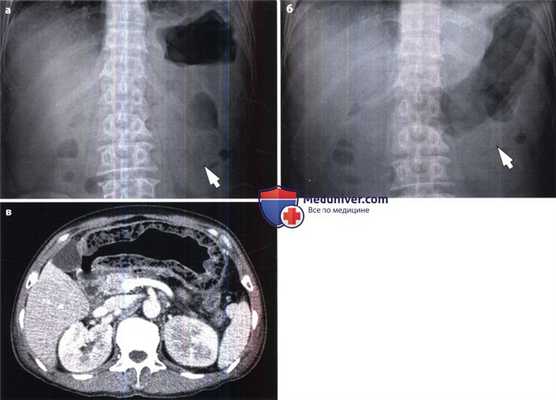

Эмфизематозный гастрит у пациента с сахарным диабетом.

(а) На рентгенограмме брюшной полости в прямой проекции выявлены прослойки и пузырьки газа (стрелка) в стенке желудка.

(б) При рентгенографии брюшной полости в положении лежа установлено, что скопление газа (стрелка) имеет одинаковую локализацию в желудке независимо от перемены положения тела. Это информативный признак, позволяющий отличить газ от остатков пищи, которые изменяют свою локализацию в зависимости от положения тела.

(в) При КТ с контрастированием выявлено диффузное утолщение стенки желудка со скоплением воздуха внутри нее, что служит характерным признаком эмфизематозного гастрита.